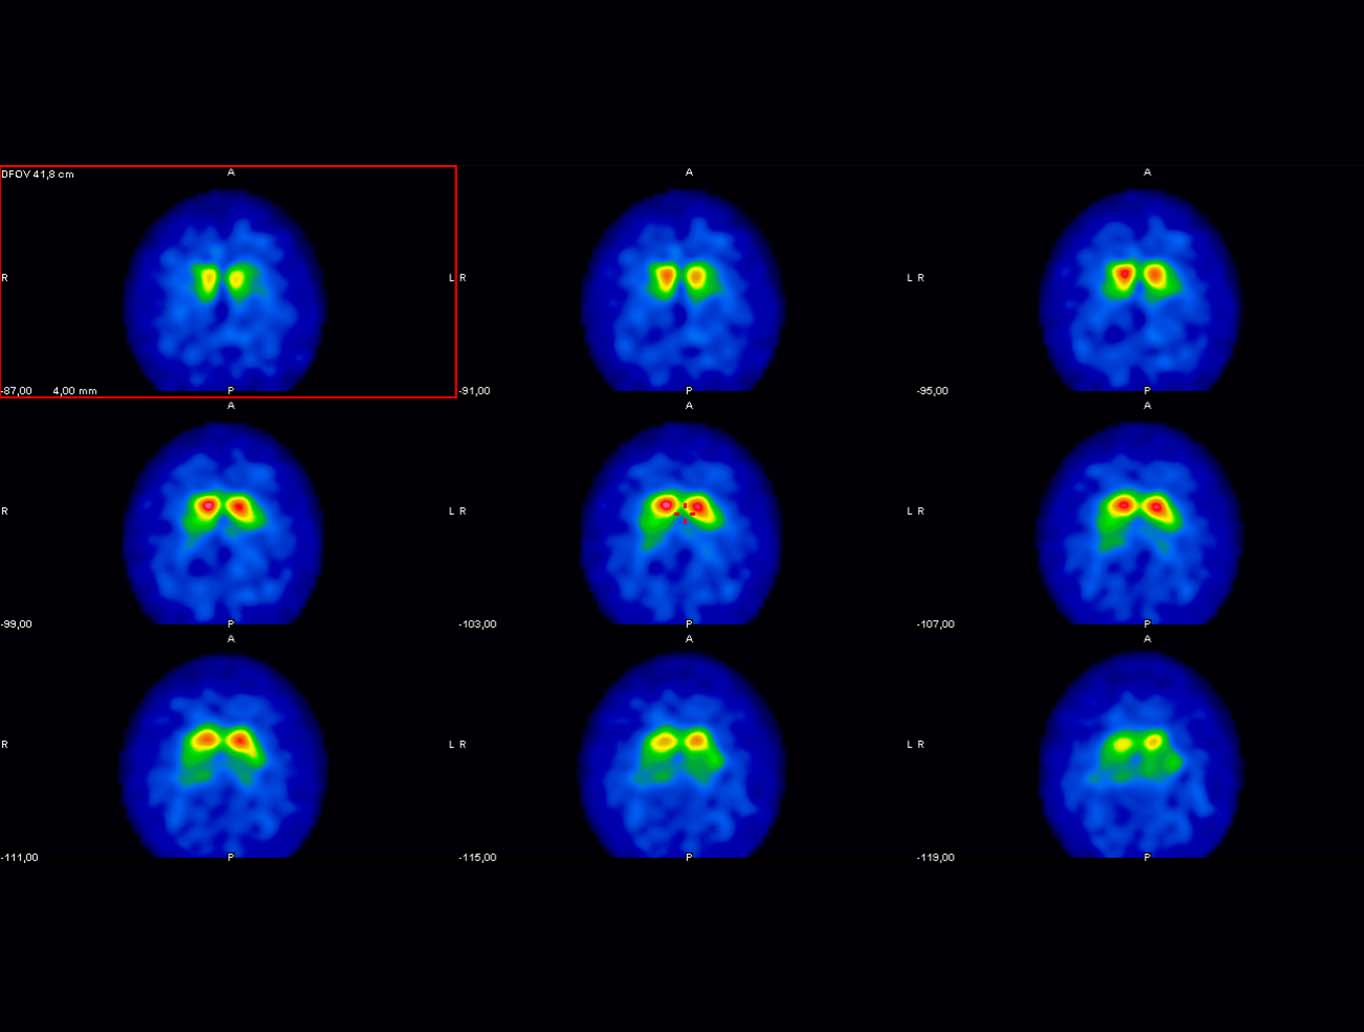

Diese Methode wird für viele Organe genutzt, etwa für die Nieren, Lunge, Gehirn oder das Lymphsystem. Auch Blutungen, Entzündungen und Tumore können so erkannt werden. Die Bilder werden entweder planar oder in SPECT/CT oder PET/CT-Technik erstellt.

In der Diagnostik geht es im Schwerpunkt um Schilddrüsenuntersuchungen, Untersuchungen zur Durchblutung des Herzens und der Lunge sowie der Skelettszintigrafie. Mit der PET/CT beurteilen wir die Ausbreitung von Tumorerkrankungen, nutzen sie aber auch zur Suche nach Entzündungsherden und zur Beurteilung des Hirnstoffwechsels.

Für „Positronen-Emissions-Tomographie“ steht die Abkürzung „PET“. Von Stoffwechselvorgängen werden bei diesem Verfahren dreidimensionale Abbildungen im Körper gemacht. Für diese Bilder wird ein Tracer – eine Substanz zum Aufspüren von Stoffwechselvorgängen – benutzt. Es reichert sich in bestimmten Zelltypen und damit in definierten Körperregionen an. Dabei zeigt es Bereiche mit erhöhter Stoffwechselaktivität an. PET ist eins der wichtigsten bildgebenden Verfahren überhaupt.

Beim PET-CT wird dieses Verfahren gezielt mit der Computertomographie (CT) verbunden. Dadurch werden die abgebildeten Stoffwechselvorgänge ganz genau in den zugehörigen Körperregionen zusammen abgebildet werden. PET bildet die Stoffwechselprozesse im Körper ab, während CT die zugehörige Anatomie zeigt.